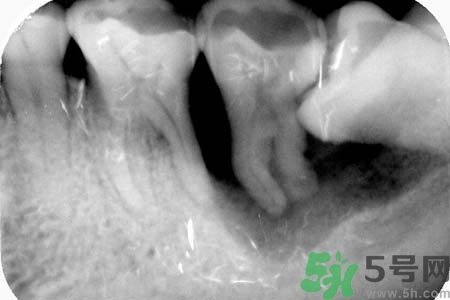

智齒橫著長(zhǎng)在拔除的時(shí)候需要遵循一些原則。正常情況下,生長(zhǎng)情況沒(méi)有出現(xiàn)異常的智齒盡量要保留下來(lái),不要隨便進(jìn)行拔除。特別是那些生長(zhǎng)了很多年的智齒。只有當(dāng)智齒非正常生長(zhǎng),出現(xiàn)一些臨床癥狀的時(shí)候,才有拔除的需要。而且,在進(jìn)行拔除手術(shù)之前,一定要先拍攝牙片,確定智齒生長(zhǎng)異常再進(jìn)行拔除。還有,發(fā)炎的智齒也必須要拔掉。但是如果炎癥消退,而且沒(méi)有出現(xiàn)復(fù)發(fā)的話(huà),也可以不拔。

智齒橫著長(zhǎng)具有很大的危害,它會(huì)擠壓附近的牙齒,嚴(yán)重時(shí)會(huì)導(dǎo)致整排的牙齒看起來(lái)都不整齊。而且還會(huì)影響到患者的咀嚼功能。智齒阻生跟前牙間會(huì)容易殘留食物殘?jiān)?,積累細(xì)菌,引發(fā)齲齒或冠周炎。如果一旦出現(xiàn)冠周炎就會(huì)反復(fù)地發(fā)作。智齒橫著長(zhǎng)還會(huì)影響牙齒的咬合,長(zhǎng)期下來(lái)更會(huì)引發(fā)下頜疼痛、夜磨牙等。很多20多歲左右的年輕人,總是覺(jué)得牙齒疼痛,去醫(yī)院檢查都會(huì)發(fā)現(xiàn)是因?yàn)橹驱X橫著長(zhǎng)。但是智齒橫著長(zhǎng)很難察覺(jué),通常都是是引發(fā)了疼痛,患者才會(huì)開(kāi)始所察覺(jué)。

智齒的生長(zhǎng),關(guān)鍵看你牙床的位置、頜骨的空間是否夠,如果夠,是根本不會(huì)疼的。智齒如果被阻生在頜骨里,或根本就不見(jiàn)萌出。或是導(dǎo)致其他牙齒排列擁擠或移位,從而使局部牙齒出現(xiàn)齲齒、感染或牙齦疼痛。阻生的智齒在頜骨內(nèi)的位置也是異常的,有時(shí)甚至呈水平阻生。這種情況最好是拔去。另外,你疼痛得不行了,也最好去醫(yī)院處理掉。其他情況最好就不要去拔,由于智齒在口腔最內(nèi)側(cè),最難操作,操作不當(dāng)反而有害。用麻藥也不是什么好東西。在排除以上情況,你不想拔的話(huà),給你幾點(diǎn)建議: